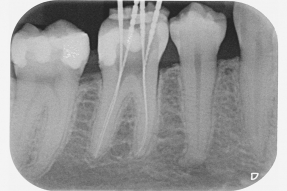

Wurzelkanalbehandlung – Moderne Technik bringt über 95 % langfristigen Erfolg

Wurzelbehandlungen (Endodontie) gehören zu den anspruchsvollsten Disziplinen innerhalb der Zahnmedizin: Spezielle Instrumente zur Wurzelkanalbehandlung Wurzelkanäle können stark gekrümmt sein. Mit einfachen Instrumenten sind solche Kanäle nicht immer vollständig zu reinigen und zu erweitern. Deshalb verwenden wir spezielle und hoch flexible Nickel-Titan-Instrumente. Mit ihnen sind wir in der Lage auch extrem feine und gekrümmte Kanäle maschinell zu bearbeiten und so nur schwer zu behandelnde Zähne noch zu retten. Außer der mechanischen Reinigung der Wurzelkanäle müssen diese auch durch desinfizierende Spülungen von Bakterien befreit werden. Wir verwenden effektive Desinfektionslösungen, um eine größtmögliche Keimfreiheit der Wurzelkanäle zu erzielen. Bakteriendichte Wurzel- und Zahnfüllungen Wurzelkanäle sind im Verlauf unterschiedlich dick und sie können Verzweigungen und Nebenkanäle haben. Wenn diese nicht abgedichtet werden, bleiben Hohlräume für Bakterien. Um das zu vermeiden, wenden wir in unserer Praxis ein modernes 3D-Verfahren an, bei dem die Wurzelkanäle in allen ihren Feinheiten ausgefüllt werden.

Die Pulpa (der „Nerv“) eines Zahnes ist einerseits sehr komplex und verästelt. Andererseits machen ihre kleinen Dimensionen die Behandlung zu einer schwierigen Aufgabe.

Deshalb ist die Erfolgsquote bei konventionell durchgeführten Wurzelbehandlungen relativ gering: Sie liegt bei nur 50–60 %. Wir haben langjährige Erfahrung und wenden moderne Methoden und Materialien an, um die Erfolgsquote zu erhöhen: Auf über 95 %! Hochwirksame desinfizierende Spülungen

Hochwirksame desinfizierende Spülungen